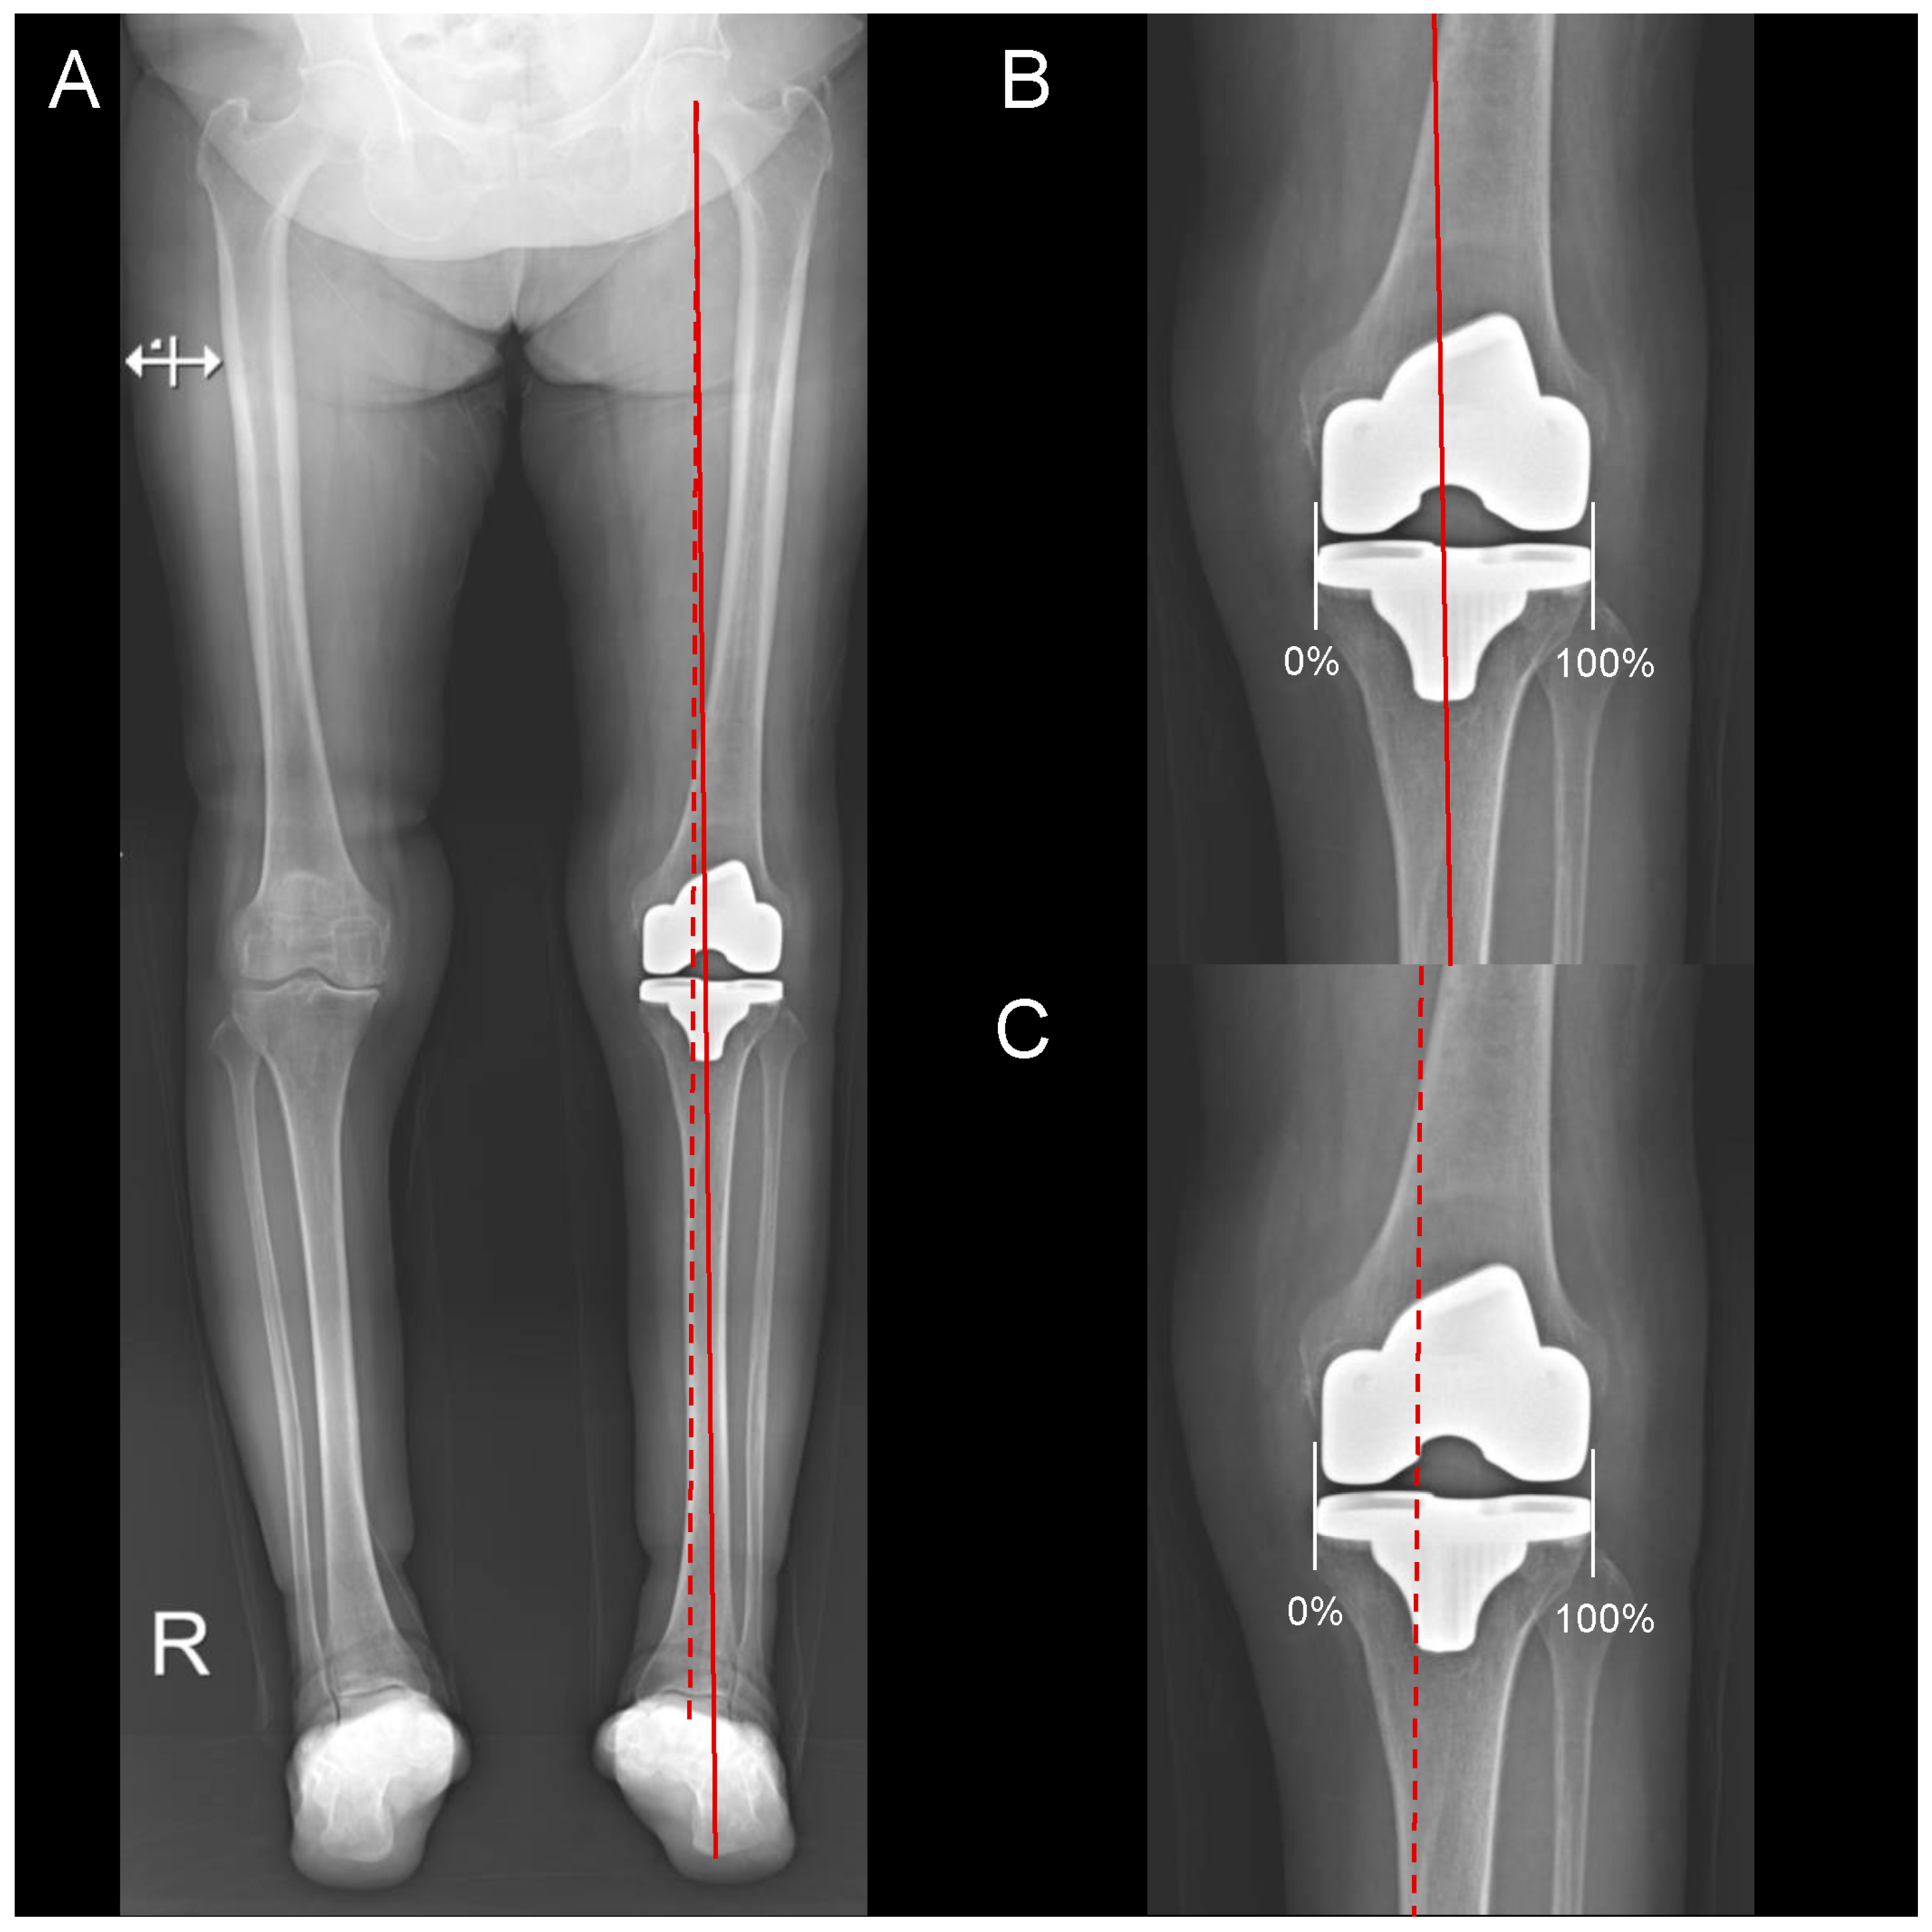

2.3. Radiographic Assessment

| Weight-bearing position in the knee joint § | |||

| Traditional MA ratio | 42.6 ± 7.6 | 48.3 ± 8.0 | <0.001 |

| GA ratio | 48.8 ± 7.0 | 53.8 ± 8.8 | 0.002 |